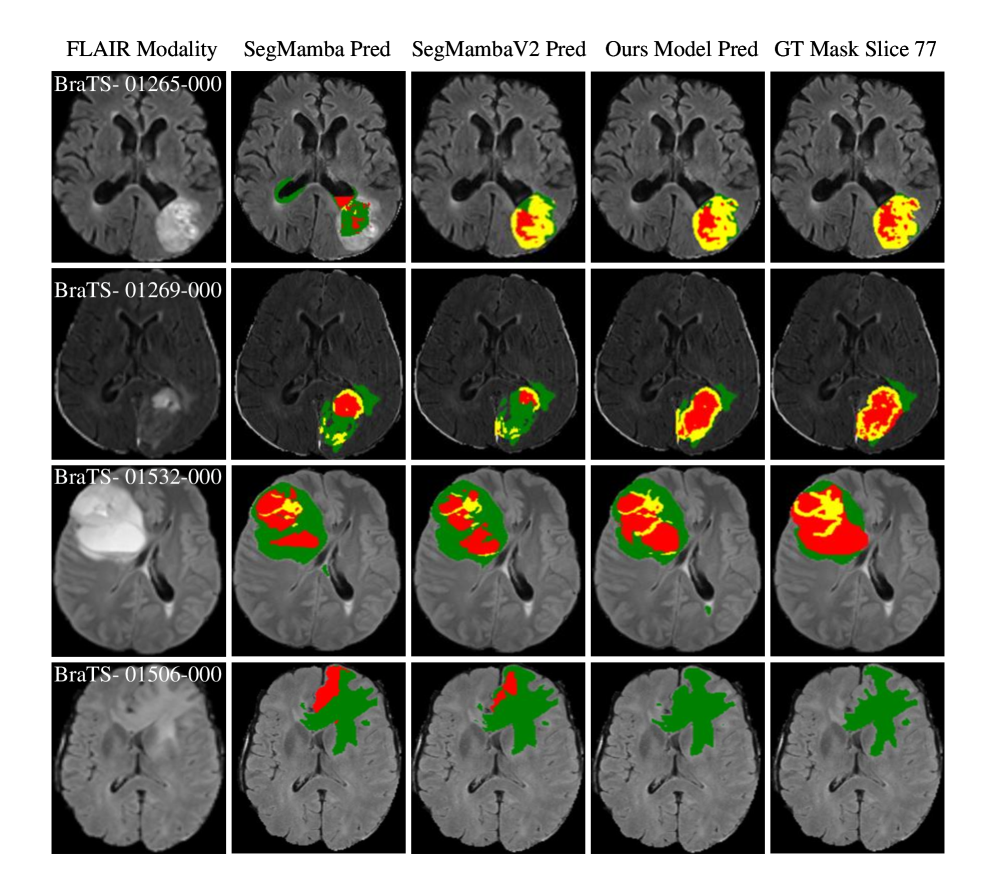

In addition to the quantitative analysis, qualitative results offer further insights into segmentation performance. Fig. 3 illustrates middle slices from systematic Fold 3 test cases, comparing predictions from SegMamba, SegMambaV2, and the proposed model. The visualizations show that our proposed model achieves more precise delineations of the enhancing tumor (yellow) and necrotic core (red), whereas the other models under-segment or miss small regions. The edema boundaries (green region) are also well preserved, highlighting the model’s ability to maintain accuracy across all tumor sub regions even under difficult conditions.